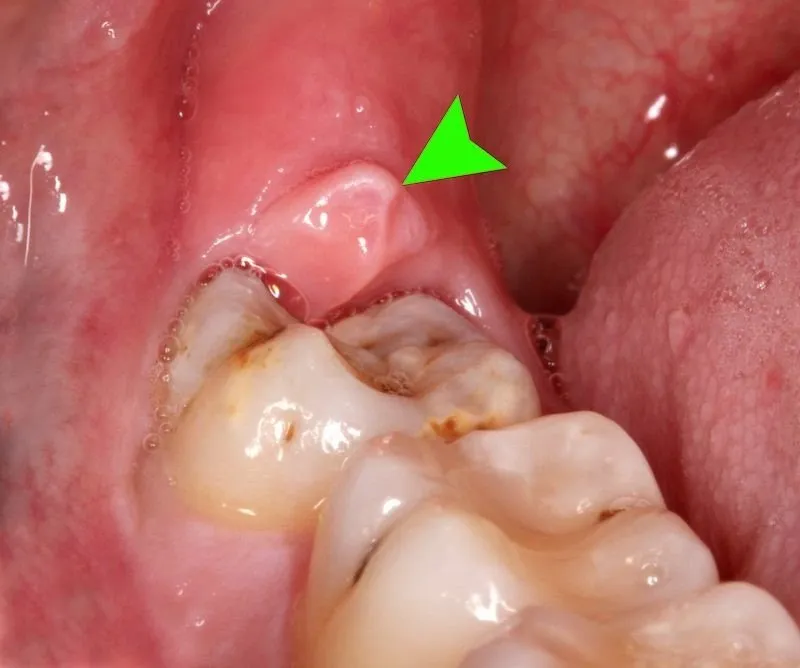

Hình ảnh viêm lợi trùm

Để giúp các bạn biết rõ bênh viêm lợi trùm, Nha khoa DrGreen xin gửi tới các bạn hình ảnh viêm lợi trùm chi tiết. Thông qua đó các bạn có thể nắm rõ và điều trị kịp thời. Cụ thể như sau: